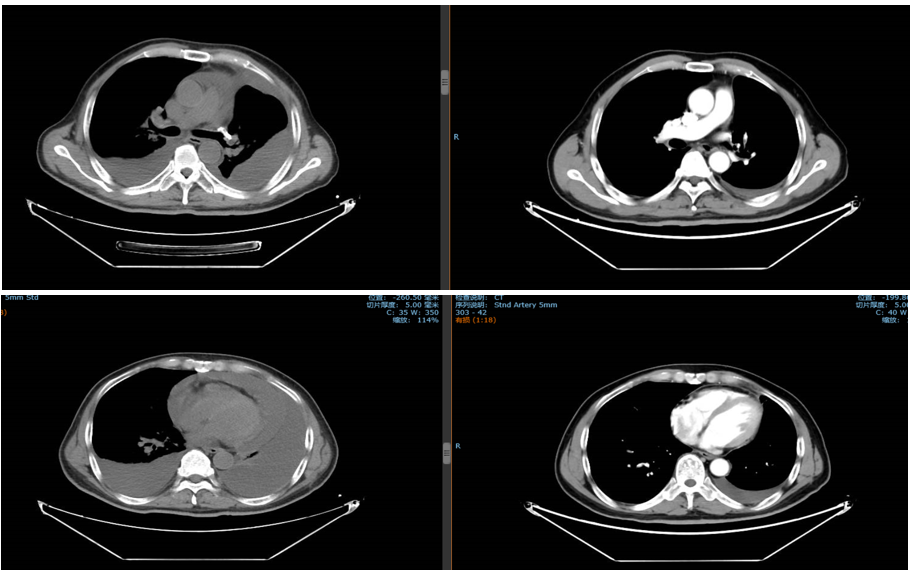

免疫联合化疗(2022年12月):紫杉醇+卡铂+PD-1抑制剂+贝伐珠单抗,共6周期。治疗后积液显著吸收,脑转移灶缩小。

维持治疗及随访(2023年6月至今):紫杉醇+PD-1抑制剂+贝伐珠单抗维持治疗。2025年6月MRD检测发现SMARCA4突变低丰度阳性,提示可能复发,需进一步评估。

新加坡国家癌症中心Kevin Lee Min Chua教授:在分析患者治疗情况时,我们发现其接受的系统治疗虽全面,但疾病控制效果短暂,每6个月随访便显示病情进展。同时,患者对紫杉醇+PD-1抑制剂+贝伐珠单抗维持治疗缓解不佳,这促使我们思考后续治疗策略。MRD检测揭示复发风险,却未明确复发位置。此时,借助PET-CT或脑部MRI检查,或许能定位潜在复发病灶。

中山大学肿瘤防治中心陈宝清教授:在分析脑转移病例时,关键在于患者是否已接受或考虑过放疗。在我们的临床实践中,针对脑转移,是否放疗取决于患者具体情况。若脑转移范围有限且其他病灶控制良好,放疗通常是重要选择。因此,我认为放疗在此案例中可作为优先选项。

上海交通大学附属胸科医院艾星浩教授:如果MRD从阴性转为阳性,这是重要的监测信号,但治疗方案的调整不能仅凭此一项指标。即只有当患者出现明确的疾病进展,特别是影像学上出现显著变化时,才考虑调整治疗方案。这样的判断标准能帮助避免因检测误差或早期波动而做出过激的治疗方案调整,确保治疗决策更加理性合理。

上海交通大学附属胸科医院李子明教授:患者并非EGFR驱动型,但从NGS检测结果来看,存在EGFR 19外显子缺失突变,未来我们应更多地关注这类患者。我认为目前不宜用MRD来诊断,CT影像检查对患者而言可能更具益处。

上海交通大学附属胸科医院陆舜教授:MRD虽具有一定预后价值,但目前尚缺乏足够证据支持其作为预测性生物标志物或用于临床终点评估,且在中国尚未有MRD检测获得NMPA批准。不过,若患者已接受MRD检测且结果由阴转阳,我会密切监测,直到影像检查发现复发、进展或新发病灶,再调整治疗方案。对于携带EGFR 19外显子缺失突变的患者,由于此突变对EGFR-TKI治疗的敏感性尚未明确,该患者对TKI治疗无缓解,治疗思路需跳出标准EGFR-TKI路径。对于术后局部复发的患者,通常会优先推荐放疗,但该患者拒绝这一局部治疗方案,错失最佳干预时机。鉴于患者表现为PD-1高表达,同时又不具备典型EGFR敏感突变,若患者拒绝同步放化疗,可考虑免疫治疗联合化疗作为替代方案,这已成为PD-1高表达患者的常用标准治疗策略之一。若出现寡进展,可评估是否可行局部治疗;若为系统性进展,则需考虑更换全身治疗方案,如ADC药物或双特异性抗体等。